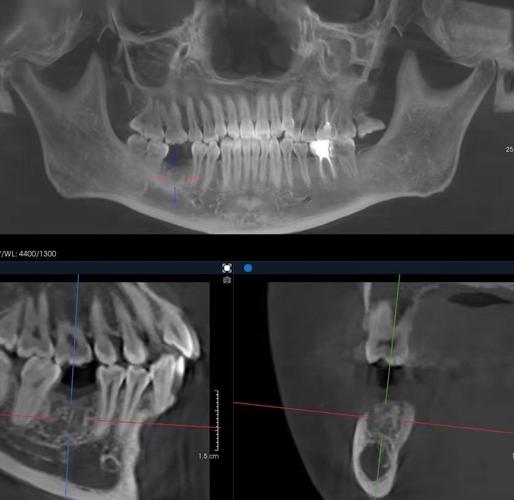

- X光片检查: 必须确认根管填充是否致密、均匀、无遗漏,根尖封闭良好(无根尖周暗影),根管治疗失败(如根尖炎症、遗漏根管)是正畸的绝对禁忌症或需要先处理。

- 影像学检查: 在正畸过程中,可能需要定期拍摄X光片(如根尖片、曲面断层片),监测根尖周状况有无变化,牙根有无吸收(根管治疗后的牙根在正畸力下更易发生吸收)。